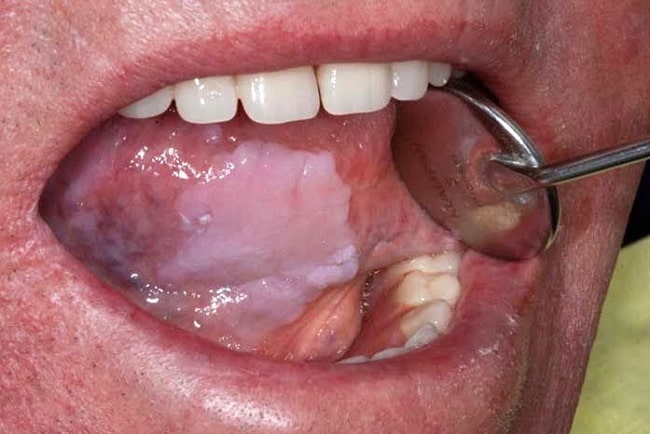

- Presencia de color rojo o una mezcla entre blanco aterciopelado y rojo en la mucosa de la boca.